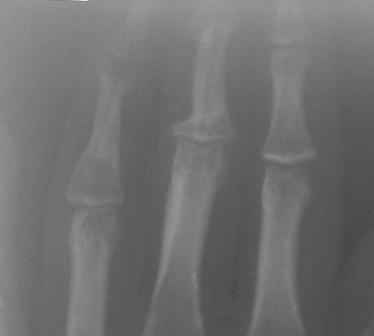

Конечно, мы во время операции будем брать материал на гистологию, а также удаление очага и замещение аутотрансплантатом тоже в плане рассматривается, как на примере, которая была представлена на форуме. правда снимки не очень качественные, прощу извинения!

Коллеги, почти уверен, что эти два случая поражения фаланг имеют различный генез. Простое выявление хрящевой ткани в биопсийном материале, увы, не дает еще диагноза.. Хотя местное лечение (если оно необходимо) может быть сходным. Единственное, не стал бы увлекаться широкими резекциями и массивными костными пластиками в детей.